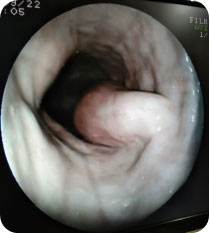

Endoscopy allows a visual examination of internal organs and body parts without invasive exploratory surgery, using fiber-optic instrumentation. Special video cameras attached to the endoscope allow viewing of the exam on a screen. The advantage of endoscopy over other methods is that it is less invasive.